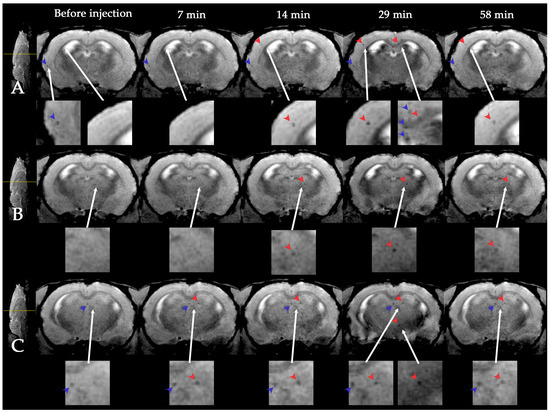

3.1. Dynamic MRI Distribution of MSCs in Ischemic Rat Brain after Intravenous Transplantation

- Namestnikova, D.; Gubskiy, I.; Kholodenko, I.; Melnikov, P.; Sukhinich, K.; Gabashvili, A.; Vishnevskiy, D.; Soloveva, A.; Abakumov, M.; Vakhrushev, I.; et al. Methodological aspects of MRI of transplanted superparamagnetic iron oxide-labeled mesenchymal stem cells in live rat brain. PLoS ONE 2017, 12, e0186717. [Google Scholar] [CrossRef] [PubMed]

- Namestnikova, D.D.; Gubskiy, I.L.; Revkova, V.A.; Sukhinich, K.K.; Melnikov, P.A.; Gabashvili, A.N.; Cherkashova, E.A.; Vishnevskiy, D.A.; Kurilo, V.V.; Burunova, V.V.; et al. Intra-Arterial Stem Cell Transplantation in Experimental Stroke in Rats: Real-Time MR Visualization of Transplanted Cells Starting With Their First Pass Through the Brain With Regard to the Therapeutic Action. Front. Neurosci. 2021, 15, 179. [Google Scholar] [CrossRef]